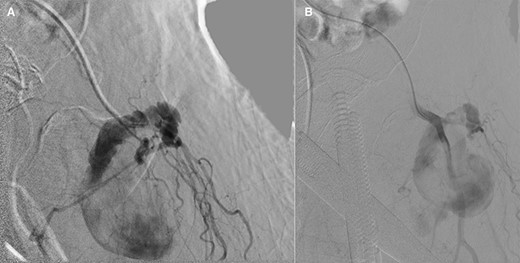

Vascular surgery was consulted and CT angiography demonstrated a large DFA pseudoaneurysm (Fig. 4A and B). Given her advanced years and comorbidities, a minimally invasive approach was recommended. The pseudoaneurysm was successfully embolized using numerous microcoils (Fig. 5). Completion angiography demonstrated complete occlusion of the pseudoaneurysm and patent superficial and DFA (Fig. 5). There were no immediate complications. After discussion with the patient, it was agreed that restarting her apixaban increased risk for her hematoma rebleeding and no anticoagulation was continued for stroke prevention.

(A and B): Frontal digitally subtracted angiography via a diagnostic catheter positioned in the proximal left DFA demonstrating a large pseudoaneurysm originating from a small DFA branch. The long, narrow and lobulated pseudoaneurysm neck can be see coursing along the cranial aspect of the pseudoaneurysm.